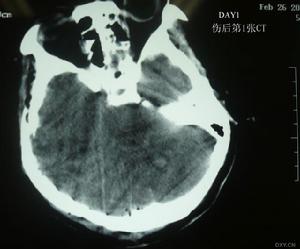

4.顱內壓增高與腦疝為繼發腦水腫或顱內血腫所致,使早期的意識障礙或癱瘓程度有所加重,或意識好轉、清醒後又變為模糊,同時有直壓升高、心率減慢、瞳孔不等大以及錐體束征等表現。CT檢查:不僅可了解腦挫裂傷的具體部位、範圍(傷灶表現為低密度區內有散在的點、片狀高密度出血灶影)及周圍踏水腫的程度(低密度影範圍),還可了解腦室受壓及中線結構移位等情況。

(5)CT和磁共振檢查,對顱腦損傷診斷也有重要意義。